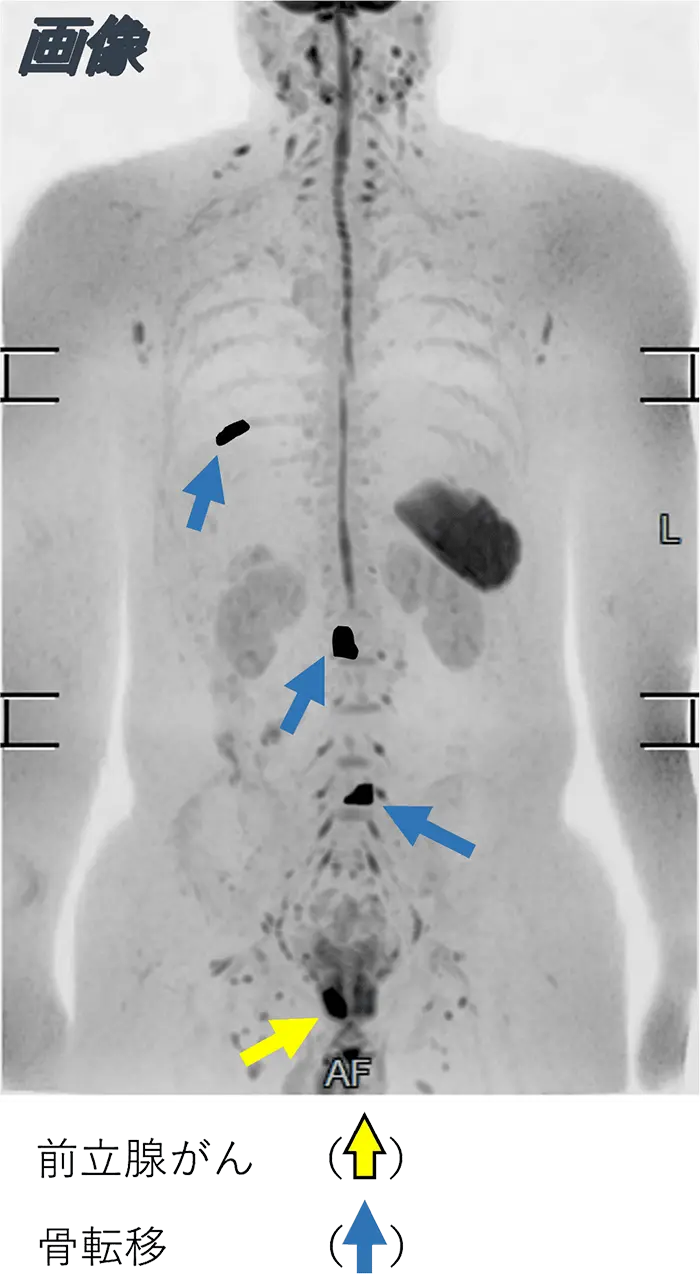

MRIを使って行なうDWIBS(ドゥイブス)法という撮影方法で、細胞密度の違いに着目し、正常な細胞の密度と悪性腫瘍などの密度の違いを抽出して悪性腫瘍を検索する検査です。放射線を使わないため被ばくがなく痛みもほとんどない、検査時間も30分程度と短いため、心身の負担を軽減しながら全身をチェックできます。被ばくの心配や造影剤の使用に心配がある方、痛みの少ない方法が良い方、一度に全身のがんの有無を調べたい方におすすめの検査です。

画像のようにがんが疑われる部分が黒く強調されます。

(※画像はイメージ画像になります)

これらの画像を基に画像診断専門の医師が結果を作成します。

がんが疑われる結果の場合は、当クリニックで精密検査を受けていただくか、治療可能な医療機関へご紹介いたします。